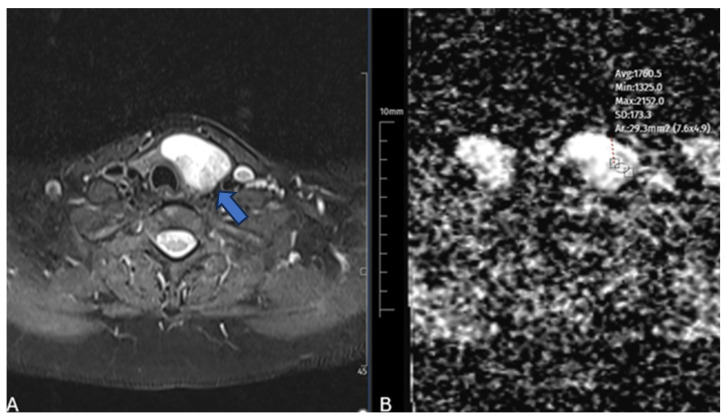

Background: Microwave ablation (MWA) is an effective, minimally invasive therapy for benign thyroid nodules; however, the treatment response varies considerably. Identifying imaging biomarkers that can predict volumetric outcomes may optimize patient selection. Diffusion-weighted MRI (DW-MRI) offers a noninvasive assessment of tissue microstructure through apparent diffusion coefficient (ADC) measurements, which may correlate with ablation efficacy. Methods: In this prospective study, 48 patients with 50 cytologically confirmed benign thyroid nodules underwent diffusion-weighted magnetic resonance imaging (DW-MRI) before minimally invasive ablation (MWA). Baseline ADC values were measured, and nodule volumes were assessed by ultrasound at baseline and 1, 3, and 6 months postprocedure. The volume reduction ratio (VRR) was calculated, and associations with baseline variables were analyzed via Pearson correlation and multivariable linear regression. ROC curve analysis was used to evaluate the diagnostic performance of ADC in predicting significant volume reduction (VRR ≥ 50%). Results: Lower baseline ADC values were strongly correlated with greater VRR at 3 months (r = -0.525, p < 0.001) and 6 months (r = -0.564, p < 0.001). Multivariable regression revealed that the baseline ADC was the sole independent predictor of the 6-month VRR (β = -19.52, p = 0.0004). ROC analysis demonstrated excellent discriminative performance (AUC = 0.915; 95% CI: 0.847-0.971), with an ADC cutoff of 2.20 × 10-3 mm2/s yielding 90.9% sensitivity and 83.3% specificity for predicting a favorable volumetric response. Conclusions: Baseline ADC values derived from DW-MRI strongly predict volumetric response following microwave ablation of benign thyroid nodules. Incorporating ADC assessment into preprocedural evaluation may enhance patient selection and improve therapeutic outcomes.